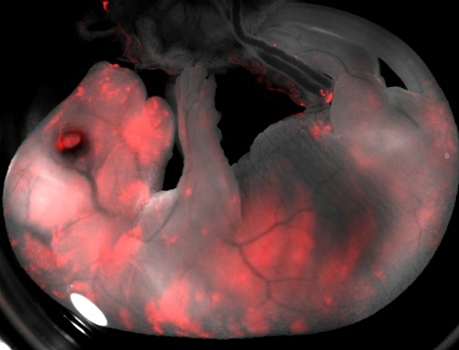

Созданы эмбрионы-химеры человека и свиньи

Впервые ученым удалось вырастить эмбрионы-химеры, которые состояли как из клеток свиньи, так и из клеток человека, хотя доля последних составляла меньше 0,001%, сообщают СМИ. После того, как ученые вживили человеческие стволовые клетки в эмбрионы свиньи, эмбрион на 28 дней подсаживали самке свиньи, передает Би-би-си со ссылкой на Cell. Следует отметить, что на протяжении всех 28 дней развивались только 186 эмбрионов из 2, 75 тыс., но, судя по признакам, человеческие клетки продолжали работать как часть организма. Как заявил один из авторов исследования профессор Хуан Карлос Исписуа Бельмонте из Института биологических исследований Солка ,«впервые человеческие клетки росли внутри крупного животного». Он указала, что в результате эволюции организм человека стал сильно отличаться от организма свиньи, в частности, беременность свиньи длится всего четыре месяца, поэтому нет ничего удивительного в том, что большинство эмбрионов не развивались. Для того, чтобы результаты подобных экспериментов можно было использовать с практической пользой, доля человеческих клеток в эмбрионе должна быть увеличена до 0,1-1%. Тогда такие эмбрионы можно будет использовать для первичных испытаний лекарств, изучения начала развития человеческого организма в целом и отдельных болезней у людей.